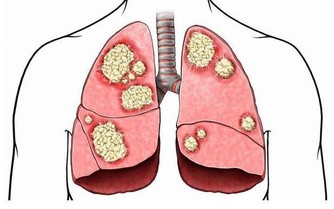

3、糖尿病患者

糖尿病分為神經病變型、缺血型、和混合型。神經病變型的部分患者,可以表現為腿足感覺奇冷,怕冷。因此,熱水泡腳很容易,成為一個舒適的選擇。悲劇在於:神經病變一旦存在,患者對痛覺、水溫的感覺,反饋機制失靈。因此患者往往會不斷加熱水,哪怕已經嚴重燙傷,也渾然不知。

而缺血型糖尿病足患者面臨的問題,則與上面提到的動脈閉塞症患者的情況相似。

所以假如患有以上這些病症,就建議不要天天泡腳,非旦不能養生,還可以致殘!